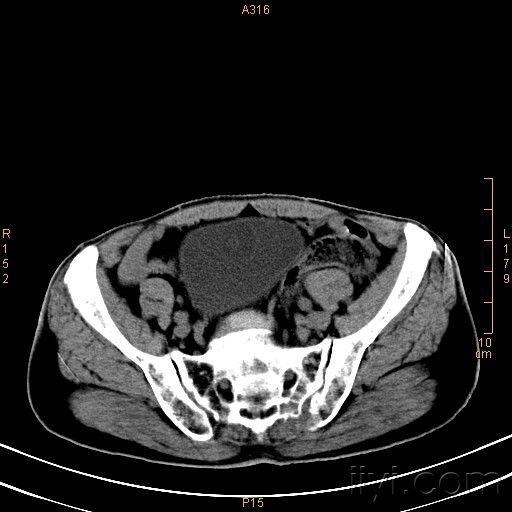

盆腔占位/ct/公布结果/100128

图片尺寸918x816